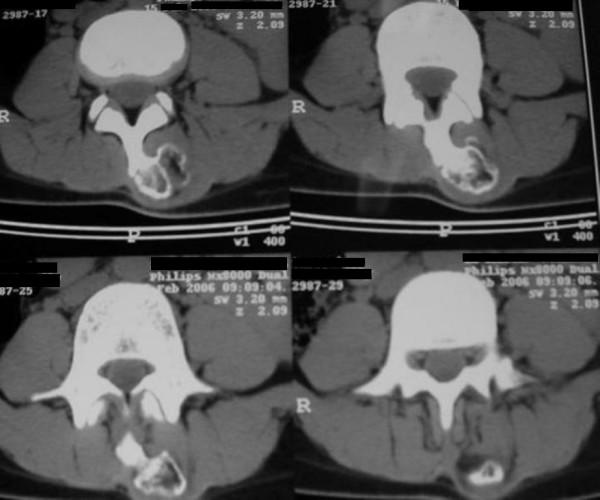

Solitary osteochondromas, which are the most common benign bone tumors of long bones, are rarely found in the vertebral column. A 16-year-old female patient presented with a hard palpable mass at lower lumbar region like a congenital deformity. Plain radiography illustrated a well-defined solid mass arising from the posterior elements of the L3 and ruled out any congenital anomalies. A computed tomography scan further determined a mass that arose from the spinous process of L3. The tumor was excised en bloc through a posterior approach and histopathological examination verified the diagnosis of osteocondroma.Osteochondromas are rarely found in the spine, when present in the spine, however, have a predilection for cervical or upper thoracic region arising usually from lamina of vertebrae and are rare in lumbosacral region and very rare at spinous process of the vertebrae.We present a case of osteochondroma locates in lumbar region and spinous process of vertebrae with unusual presentation and was considered clinically as congenital lumbar kyphosis.

孤立性骨软骨瘤是长骨最常见的良性骨肿瘤,很少见于脊柱。一名16岁女性患者,下腰部可触及硬性肿块,类似先天性畸形。X线平片显示L3后部有一个边界清晰的实性肿块,排除了任何先天性异常。计算机断层扫描进一步确定肿块起源于L3棘突。通过后路整块切除肿瘤,组织病理学检查证实为骨软骨瘤。骨软骨瘤很少见于脊柱,然而,当出现在脊柱时,多发生于颈椎或上胸椎区域,通常起源于椎板,在腰骶部区域罕见,在椎体棘突处非常罕见。我们报告一例位于腰椎区域和椎体棘突的骨软骨瘤,表现不寻常,临床上曾被认为是先天性腰椎后凸。